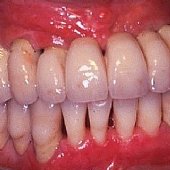

Bilder: Zahnimplantate bei Zahnlosigkeit im Unterkiefer

• Darstellung des Kieferkammes eines zahnlosen Unterkiefers.